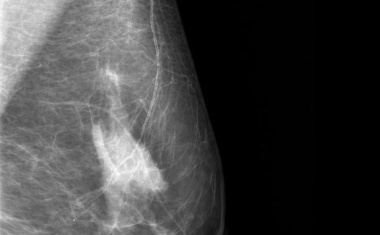

Eine neue Software unterstützt Mediziner dabei Brustkrebs bereits im frühen Stadium zu entdecken. Die KI-basierte Mammographie steht allen Patientinnen zur Verfügung und erhöht ihre Überlebenschance.

Das Leitlinienprogramm Onkologie hat die S3-Leitlinie Früherkennung, Diagnostik, Therapie und Nachsorge des Mammakarzinoms aktualisiert.